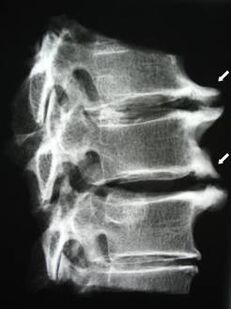

Бастапқы кезеңдерде, остеохондроз MRI көмегімен анықталады. Кейін патологияны радиографияны қолдану арқылы диагноз қоюға болады. Жатыр мойны омыртқасының радиографтарында омыртқалар арасындағы қашықтықтың төмендеуі, қырылықтардың патологиялық өзгерістері және остеофитоздар байқалады.